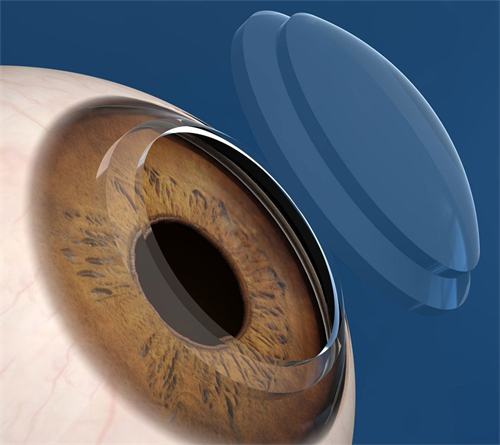

黑科技:3mm微切口植入,无需缝合,术后次日可视物,适合大泡性角膜病变